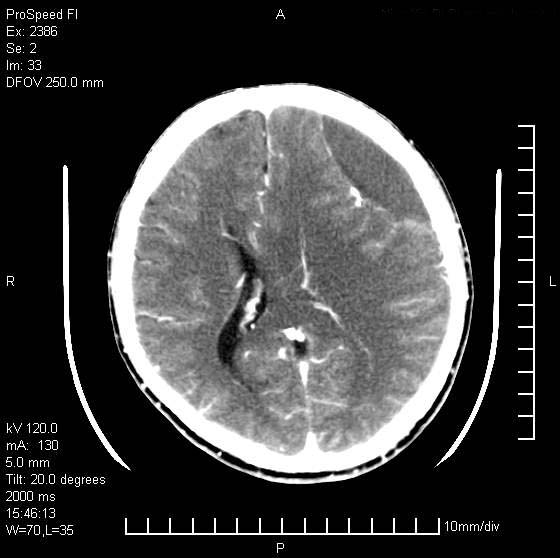

以下是引用天南地北在2007-9-19 18:43:00的发言:[br]典型慢性硬膜外血肿[br][br][本贴已被 天南地北 于 2007-9-19 18:44:11 修改过]

以下是引用曼一拍在2007-9-20 11:06:00的发言:[br]支持慢性硬膜下血肿.[br]慢性硬膜下积液:血肿有包膜,ct值稍高于脑脊液,增强可有染色。不典型者血肿可多呈梭形.是硬脑膜与蛛网膜之间的潜在腔隙内的血肿。[br]鉴别:[br]1\\硬膜外血肿:是颅脑外伤后脑膜或板障内血管破裂,血液在颅骨与硬膜之间积聚所致.通常是脑膜动脉破裂,也可因静脉窦破裂或颅骨的板障静脉出血,发生于外伤的着力部,常与颅骨骨折并存。脑膜动脉出血则急,若是板障静脉出血在则可有慢性。[br]2\\硬膜下积液:(硬膜下水瘤)[br]是由于蛛网膜破裂,脑脊液经蛛网膜破口进入硬膜下腔不能回流。或水肿阻塞而形成。[br]ct表现:颅骨内板下方新月形低密度区近似脑脊液密度;占位效应清,周围无脑水肿。[br]